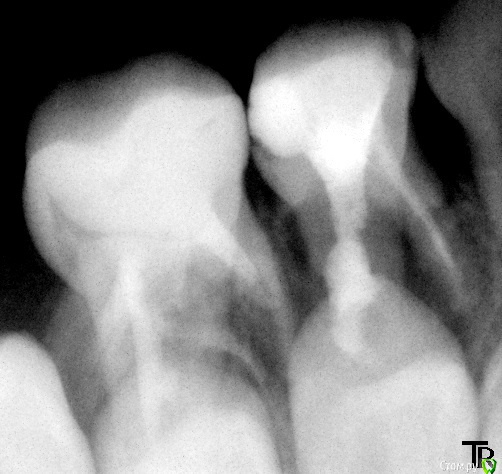

crown Опубликовано 21 апреля, 2016 Поделиться Опубликовано 21 апреля, 2016 Почти 6 лет, 64, ранее лечен, судя по запаху с пульпотеком, на десне свищ. Делал снимок в разных проекциях, дистальный корень так и не обнаружил, исчез(( Из небного потоп, экссудат, кровит адски. Вообщем положил кальсепт на 2 недели, пришли, не кровит, ничего не болит, ток зуб гуляет из стороны в сторону, повторно кальсепт на 2 недели, вот сегодня пришли, все нормально ничего не болит, только опять подвижность сильная. Запломбировал эодентом. Какой прогноз? Ссылка на комментарий